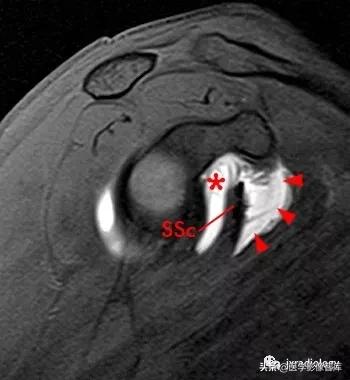

星号:superior subscapularis recess:肩胛下肌上隐窝

箭头:subcoracoid bursa:喙突下滑囊

CB:喙肱肌和肌腱

SSc:肩胛下肌腱